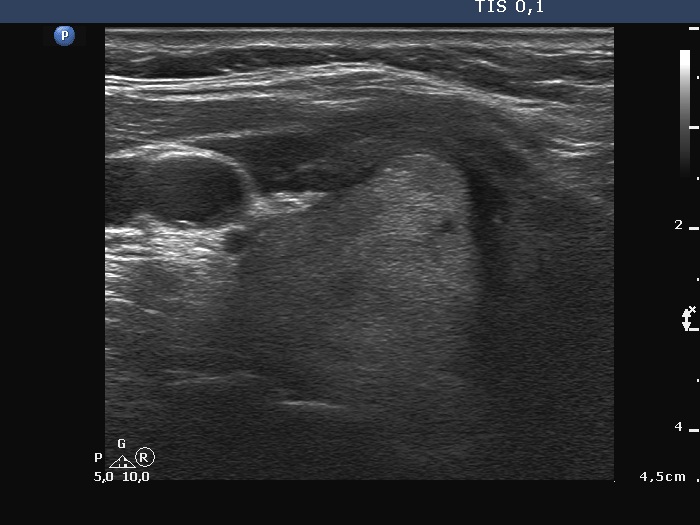

The operated thyroid - case 1388 (ultrasonographic picture 2)

Lower part of the right lobe, transverse scan. The lower part of the mass has also irregular shape.